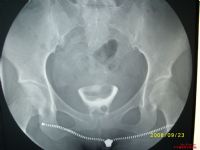

子宮輸卵管碘油造影:是檢查本症的最好方法。

(1)雙子宮:造影劑分隔從宮底直到宮頸間,陰道無分隔。

(2)重複子宮:造影劑顯示子宮、宮頸、陰道均隔為兩部分。

(3)縱隔子宮:宮腔隔為兩部分,宮頸和陰道為單腔。

(4)雙角子宮:僅為子宮底分隔。

(5)單角子宮;顯示宮腔為單角,另一側碘油不通。

(6)幼稚型子宮:碘油充盈後顯示宮腔小,子宮頸相對延長,宮頸與宮體之比為1:1~2:3(正常成年型為1:2~1:3)。

(7)子宮發育不良:宮腔小,宮頸狹窄而僵直,頸部黏膜粗大,宮體位置異常。